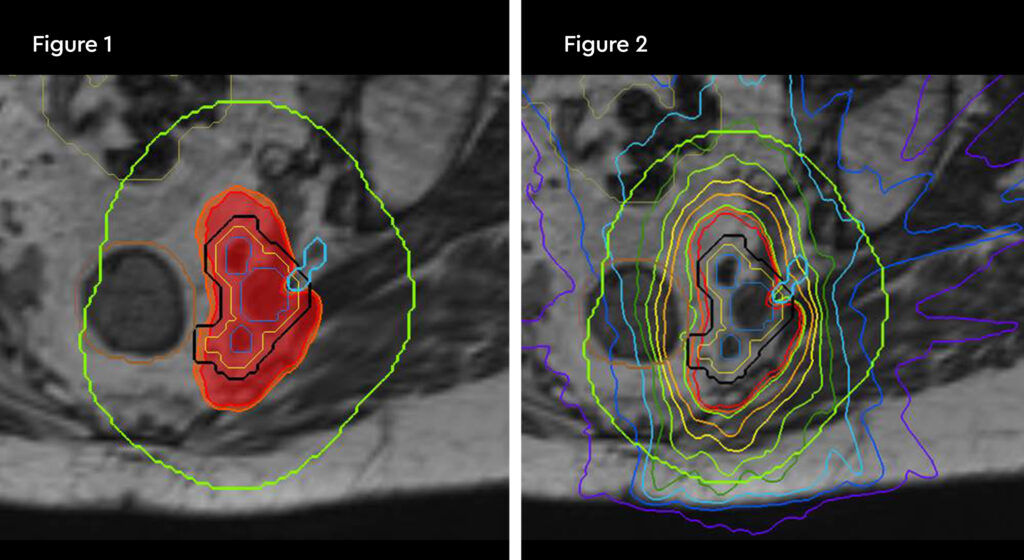

At each session, daily adaptation was performed to account for changes in the position of the prostate and for variable bladder and bowel filling. Figure 1 and figure 2 illustrate the typical differences seen between the original planning MRIdian scan and that seen on the day of treatment due to day-to-day organ movement. Figure 3 and figure 4 illustrate how these movements were accommodated with the on-table plan adaptation.

Fig 1: Original planning MRIdian scan

Fig 2: MRIdian scan at fraction 3, prostate position changed due to larger rectal diameter secondary to gas and smaller bladder

Fig 3: Prostate SABR delivery plan. Prostate volume covered by 95% isodose (green line, red arrow). Tight conformality at rectal/prostate boundary (white arrow), and rapid drop off of high dose (50% isodose, green line, green arrow) to optimise dose delivery to the prostate and limit dose to the rectum, reducing the risk of toxicity

Fig 4: Fraction 3, adapted plan, optimised for anatomy of the day. Prostate volume covered by 95% isodose (green line, red arrow). Tight conformality at rectal/prostate boundary (white arrow), and rapid drop off of high dose (50% isodose, green line, green arrow) to optimise dose delivery to the prostate and limit dose to the rectum, reducing the risk of toxicity